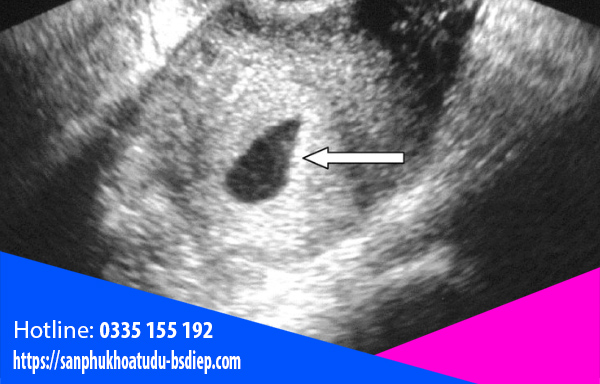

Siêu âm đầu dò

Thông thường, khi mẹ bầu bị trễ kinh lâu ngày và có hiện tượng mang thai thì đi khám. Bác sĩ khi siêu âm tử cung không thấy thai làm tổ sẽ chỉ định siêu âm ổ bụng để xem thai làm tổ ở đâu. Nếu không thấy thì sẽ tiến hành siêu âm đầu dò bằng cách dùng một dụng cụ đưa vào cổ tử cung. Đầu dò sẽ cho hình ảnh chính xác và độ nhạy cao. Siêu âm được các bộ phận buồng trứng, vòi tử cung, ống dẫn trứng… Như vậy sẽ dễ dàng tìm thấy và xác định được vị trí làm tổ của phôi thai.

Siêu âm đầu dò cũng giúp bác sĩ chẩn đoán được cả tình trạng chảy máu ổ bụng và các hiện tượng liên quan khác.